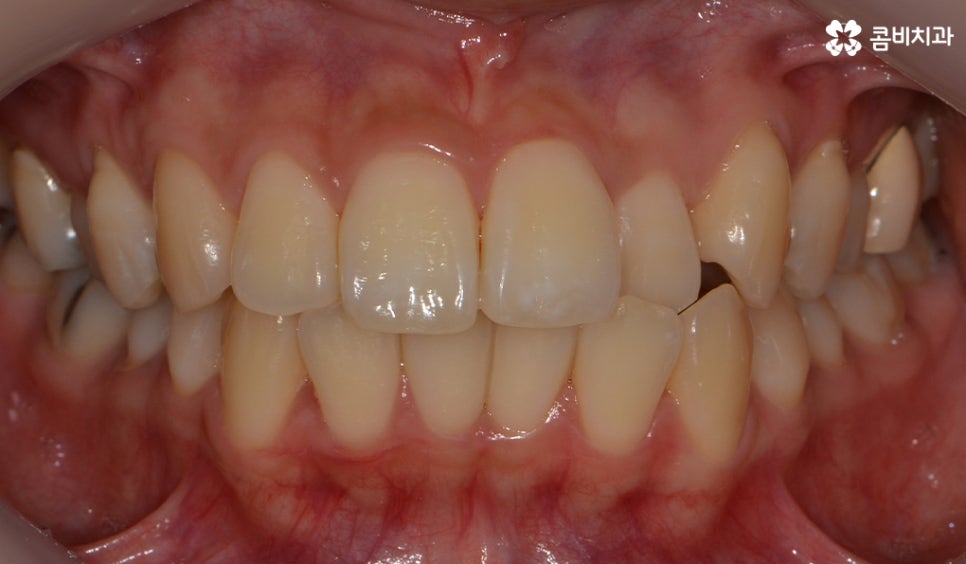

콤비교정이 완료된 모습이며 가지런한 치열 및

얼굴형과도 자연스럽게 어울리는 결과를 얻는 모습입니다.

치열 뿐 아니라 교합이 잘 맞물리고 있는 결과

자신의 얼굴과 자연스럽게 잘 어울리고 교합이 잘 맞물려야 합니다.

치열이 가지런 해지는 것은 기본이며 치아의 각도,